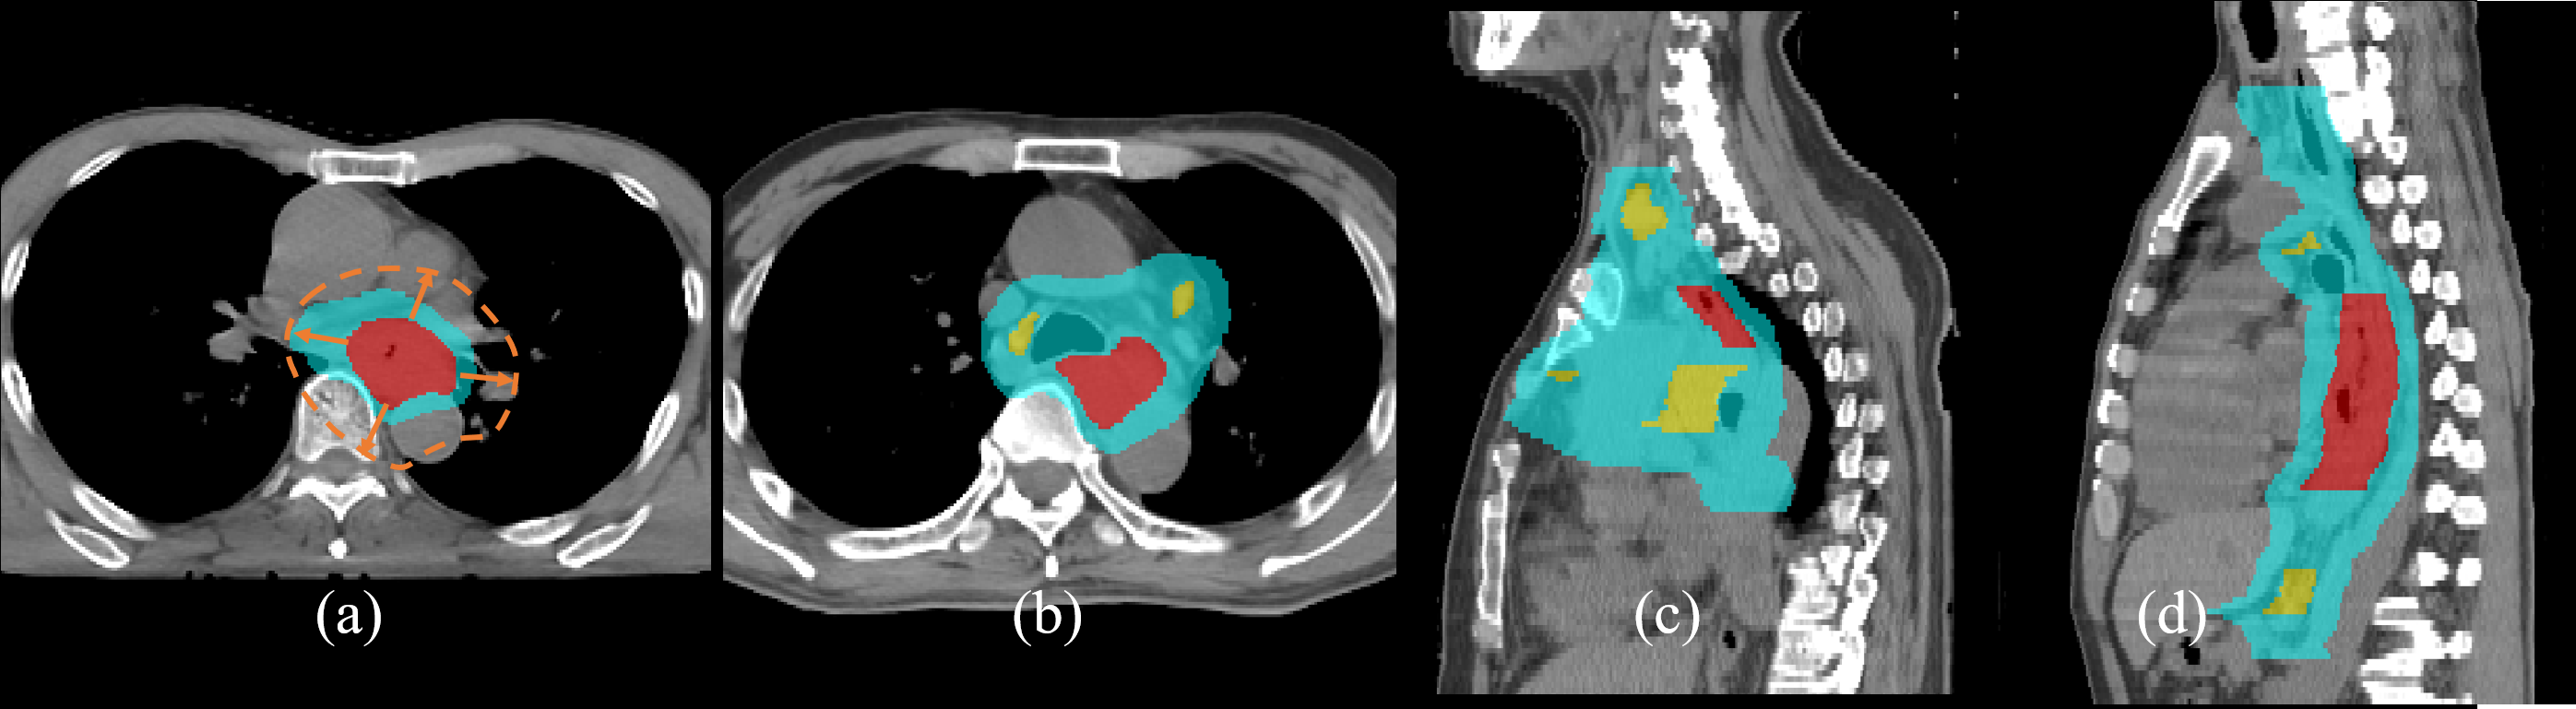

Esophageal cancer ranks the sixth in global cancer mortality [1]. As it is usually diagnosed at rather late stage [18], \acRT is a cornerstone of treatment. Delineating the 3D \acCTV on a \acRTCT scan is a key challenge in \acRT planning. As Fig. 1 illustrates, the \acCTV should spatially encompass, with a mixture of predefined and judgment-based margins, primary tumor(s), i.e., the \acGTV, regional \acpLN and sub-clinical disease regions, while simultaneously limiting radiation exposure to \acpOAR [2].

Refer to caption

Figure 1: Esophageal cancer \acsCTV delineation, where red, yellow, and cyan indicate the \acsGTV, regional \acspLN and \acsCTV, respectively. (a) shows that the \acsCTV is not a uniform margin expansion (brown-dotted line) from the \acsGTV, while (b)-(d) shows how delineation becomes more complicated when regional \acspLN are present. (c) and (d) also depict wide and long examples of esophageal \acsCTV, respectively.